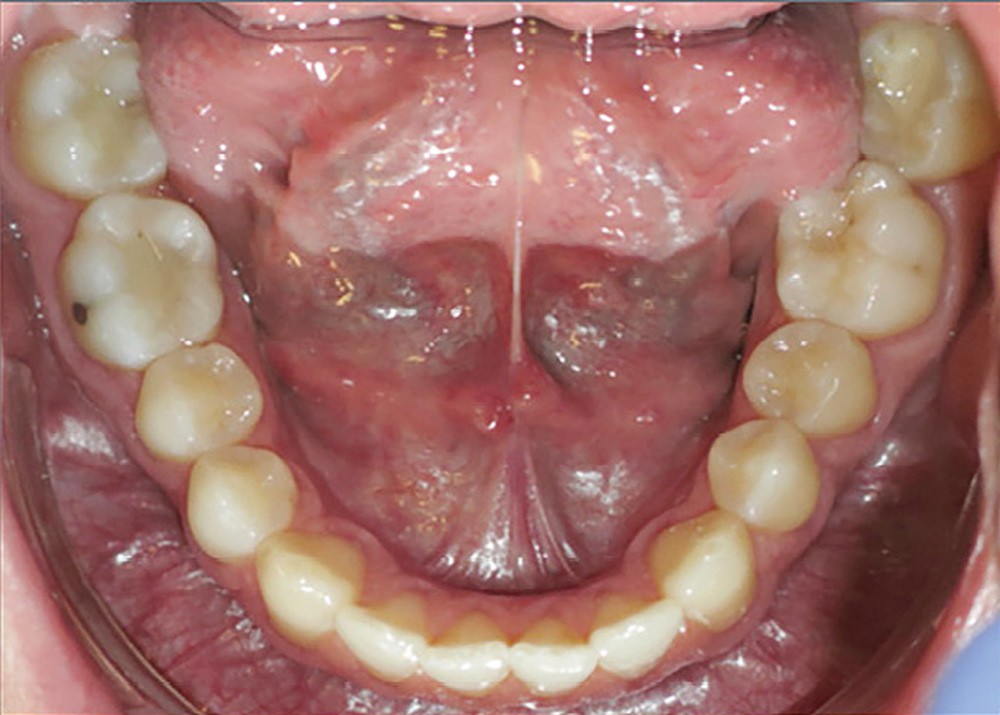

Examen endobuccal (fig. 2a-e)

L’arcade maxillaire est asymétrique, en hémi-lyre droite. Elle présente une mésio-position du secteur 1 en lien avec un encombrement antérieur estimé à 4 mm, se traduisant par une palato-position de la 12 et une rotation de la 11. On observe également des mésio-rotations des premières molaires et une palato-version incisive. L’arcade mandibulaire est ellipsoïde et présente un léger encombrement incisif (1 mm).

Concernant les relations occlusales, on observe une classe II complète subdivision droite. Le surplomb est absent et le recouvrement augmenté, estimé à 4 mm, a provoqué une usure des bords libres de 11 et 21 par attrition. Dans la dimension transversale, on constate une endoalvéolie maxillaire, ainsi qu’une concordance des médianes incisives entre elles, mais toutes deux déviées à droite par rapport au plan sagittal médian.